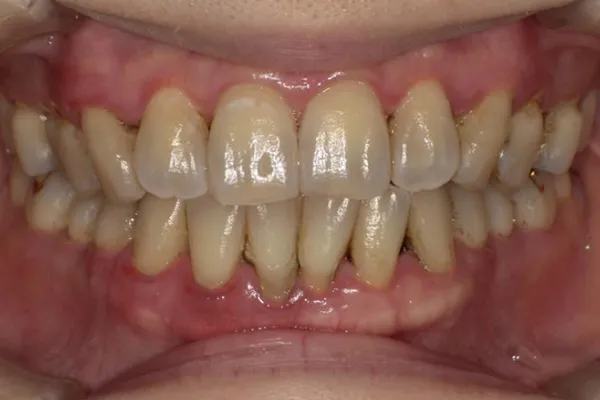

歯周組織再生療法

歯を残す最新治療

歯周病により破壊された、歯茎や骨を人工骨や成長因子などを用いて再生させる治療方法です。

将来的に抜歯となるリスクの高い歯などを歯周組織を再生させ、歯を長持ちさせることを目的とします。歯周病でダメになった歯をどうしても残したい方、歯ぐきや歯槽骨を元に戻して歯の寿命をしっかり伸ばしたい方に適応される治療方法です。 -